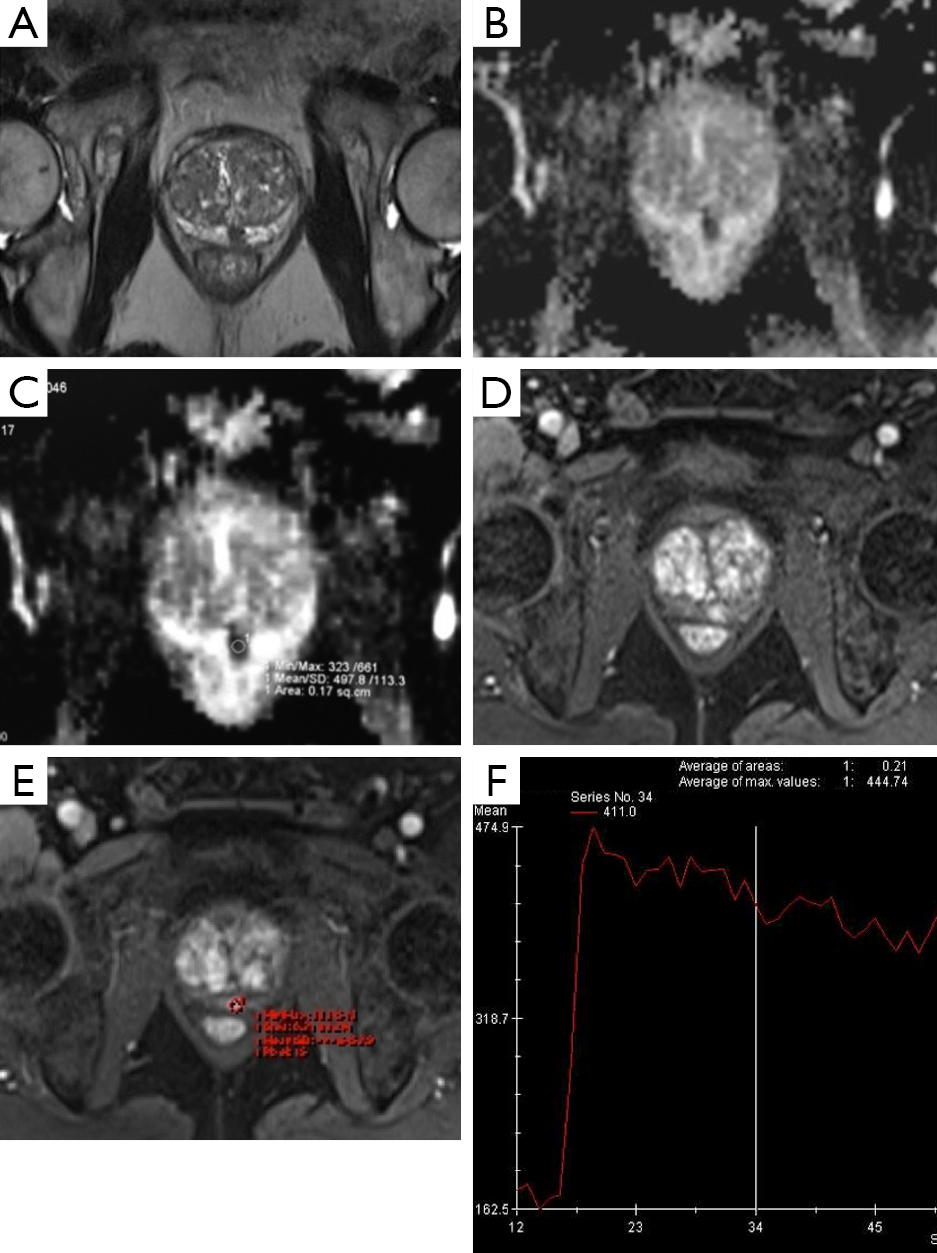

From www.researchgate.net

Multiparametric MRI of the prostate of a 63year old patient (P1)... Download Scientific Diagram What Is A Multiparametric Mri In this interview, marc a. The multiparametric mri (mpmri) is a special type of mri scan that produces a more detailed picture of your prostate gland than a standard. Multiparametric mri (mpmri) of the prostate is a novel promising tool for diagnosis of prostate cancer that might. It uses three mri techniques to provide anatomical pictures and information on the. What Is A Multiparametric Mri.